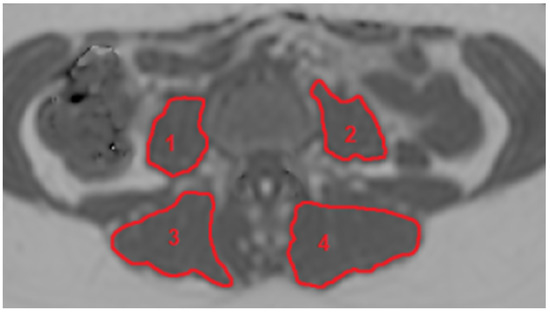

2.3. MR Image Segmentation